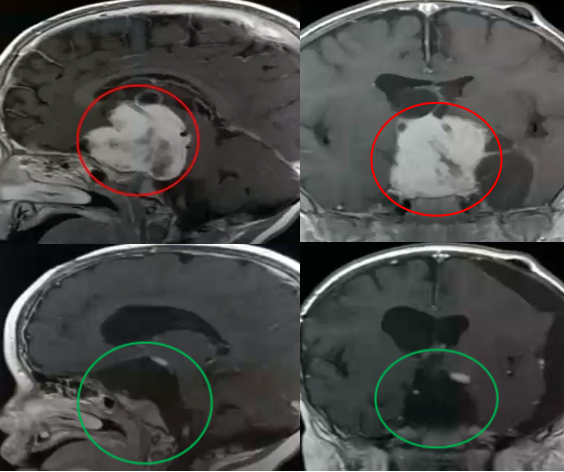

2岁的孩子,一个巨大的鞍区视路胶质瘤,让他的左眼再也看不见颜色。孩子注定要失明了吗?现实并未如此残酷,在父母的坚持下,由巴特朗菲教授主刀,经眶颧入路成功实现全切,病理为毛状黏液样星形细胞瘤。术后1年,他仍在享受着来之不易的童年,而他的小猫也始终陪伴着他度过后续的治疗时光。

7岁时查出脑瘤,第一次手术却只切了绿豆大小的肿瘤,无法确诊、无法二次手术、无法放疗……太多的阻碍让这一家人心力交瘁。尽管她始终无症状,肿瘤却从未停止生长,巴教授表示这正是手术的好时机。所幸,13岁时巴教授为她主刀的手术非常成功,病理为毛细胞星形细胞瘤。1年后,小女孩继续着自己热爱的球类运动,在阳光下挥洒汗水。